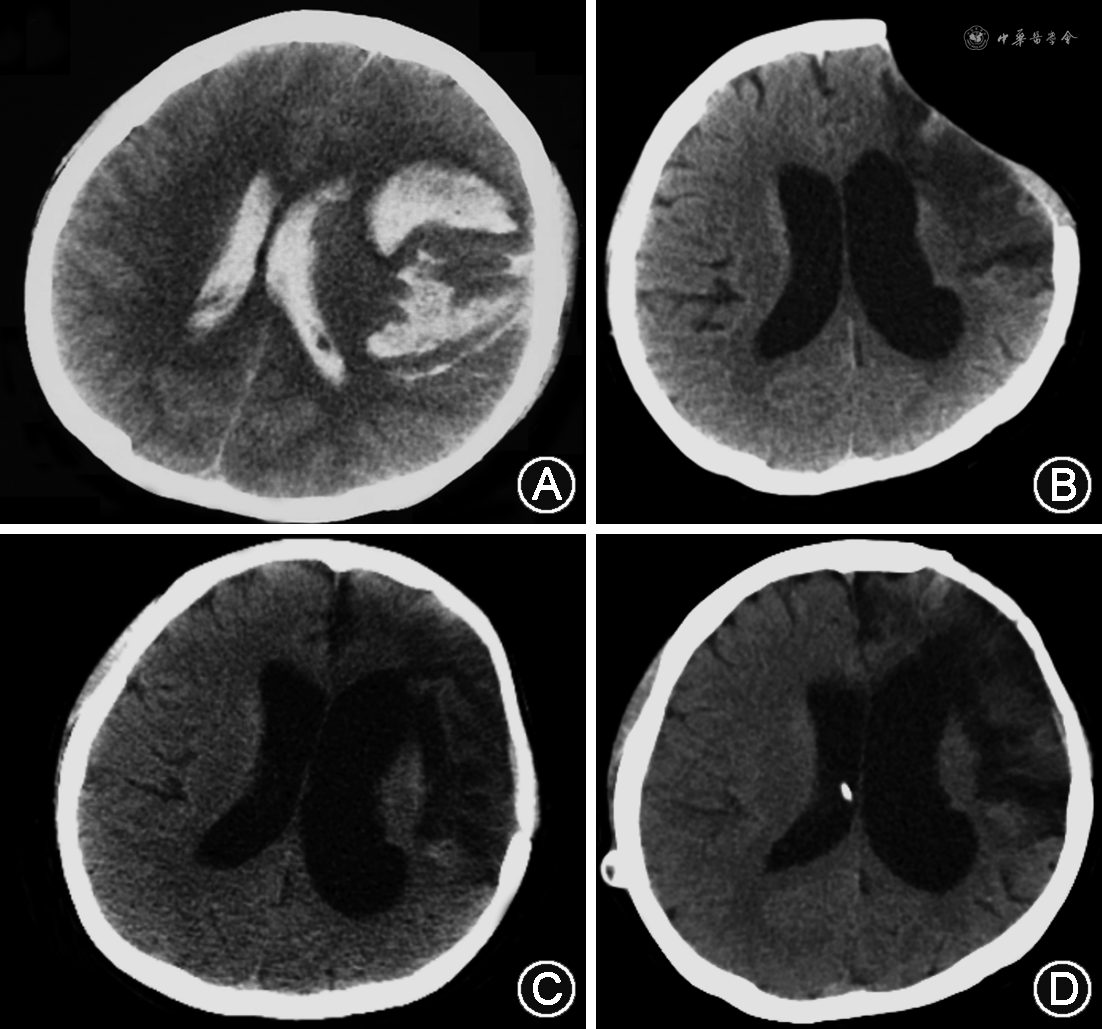

6. 影像学特征:Evans指数为0.38±0.06(91例),三脑室宽度为(15.0±3.2)mm(96例)。图1为1例典型脑出血患者发病、颅骨修补前、分流术前及分流术后的CT影像。该患者分流术后认知功能、行走能力显著改善,尿失禁完全消失,生活自理。